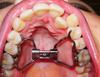

Стоит вот такой